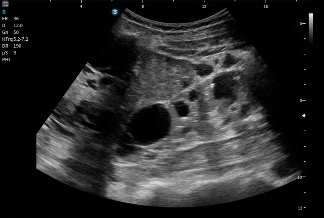

Una lesión distinta…

Durante el mismo estudio hepático se identifica una lesión que no sigue exactamente el comportamiento del resto:

- Más ecogénica

- Con contenido interno

- No completamente anecoica

El radiólogo la interpreta como posible quiste hepático complicado, como ves en las imágenes siguientes, siempre, documentar lo mejor posible.

Conviene recordar que en los cuadros de poliquistosis hepática o hepatorrenal algunos quistes pueden sangrar, infectarse o modificar su contenido, perdiendo el aspecto anecoico puro y mostrando ecos internos o mayor ecogenicidad. Debemos estar muy atentos a cualquier cambio y mirar muy bien gastando tiempo en revisar todo.